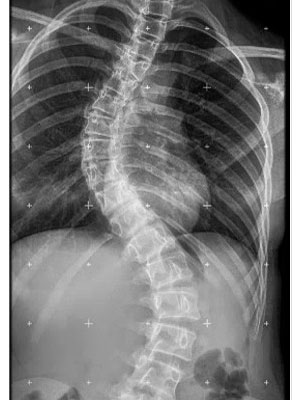

- Las radiografías deben realizarse con el paciente de pie y erguido. Para valorar mejor la alineación global de la columna vertebral, deben incluirse todas las regiones de la columna en una misma placa, en lugar de obtener radiografías individuales de cada región.

|

La radiografía que debe realizarse se denomina: Espinograma o Columna Panorámica |

¿Cómo se ve la escoliosis en la radiografía?

- La escoliosis viene definida por la región de la columna vertebral donde surge la curva (columna torácica alta, columna torácica o columna lumbar).

- La escoliosis puede localizarse en uno o más segmentos: curva simple, curvas dobles o triples.

- La dirección de la curva puede ser derecha o izquierda.

La escoliosis puede localizarse en uno o más segmentos: curva simple, curvas dobles o triples. La dirección de la curva puede ser derecha o izquierda.

Ejemplos de diferentes curvas y diversas localizaciones.